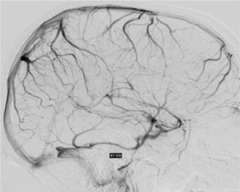

Sinus Thrombosis Figure 1: Normal

Figure 1: Normal

Cerebral venous sinus thrombosis is a rare condition when a large blood clot forms in a large vein in the brain called a dural venous sinus. The clot blocks the dural sinus and prevents the blood flow draining from the brain (Figure 1).

Brain imaging studies such as MRI and CT are commonly used to demonstrate the clot in the cerebral venous sinuses. If necessary, catheter angiography is also performed to visualize the relatively small clots or when catheter based clot-removing treatment is needed (Figure 1).